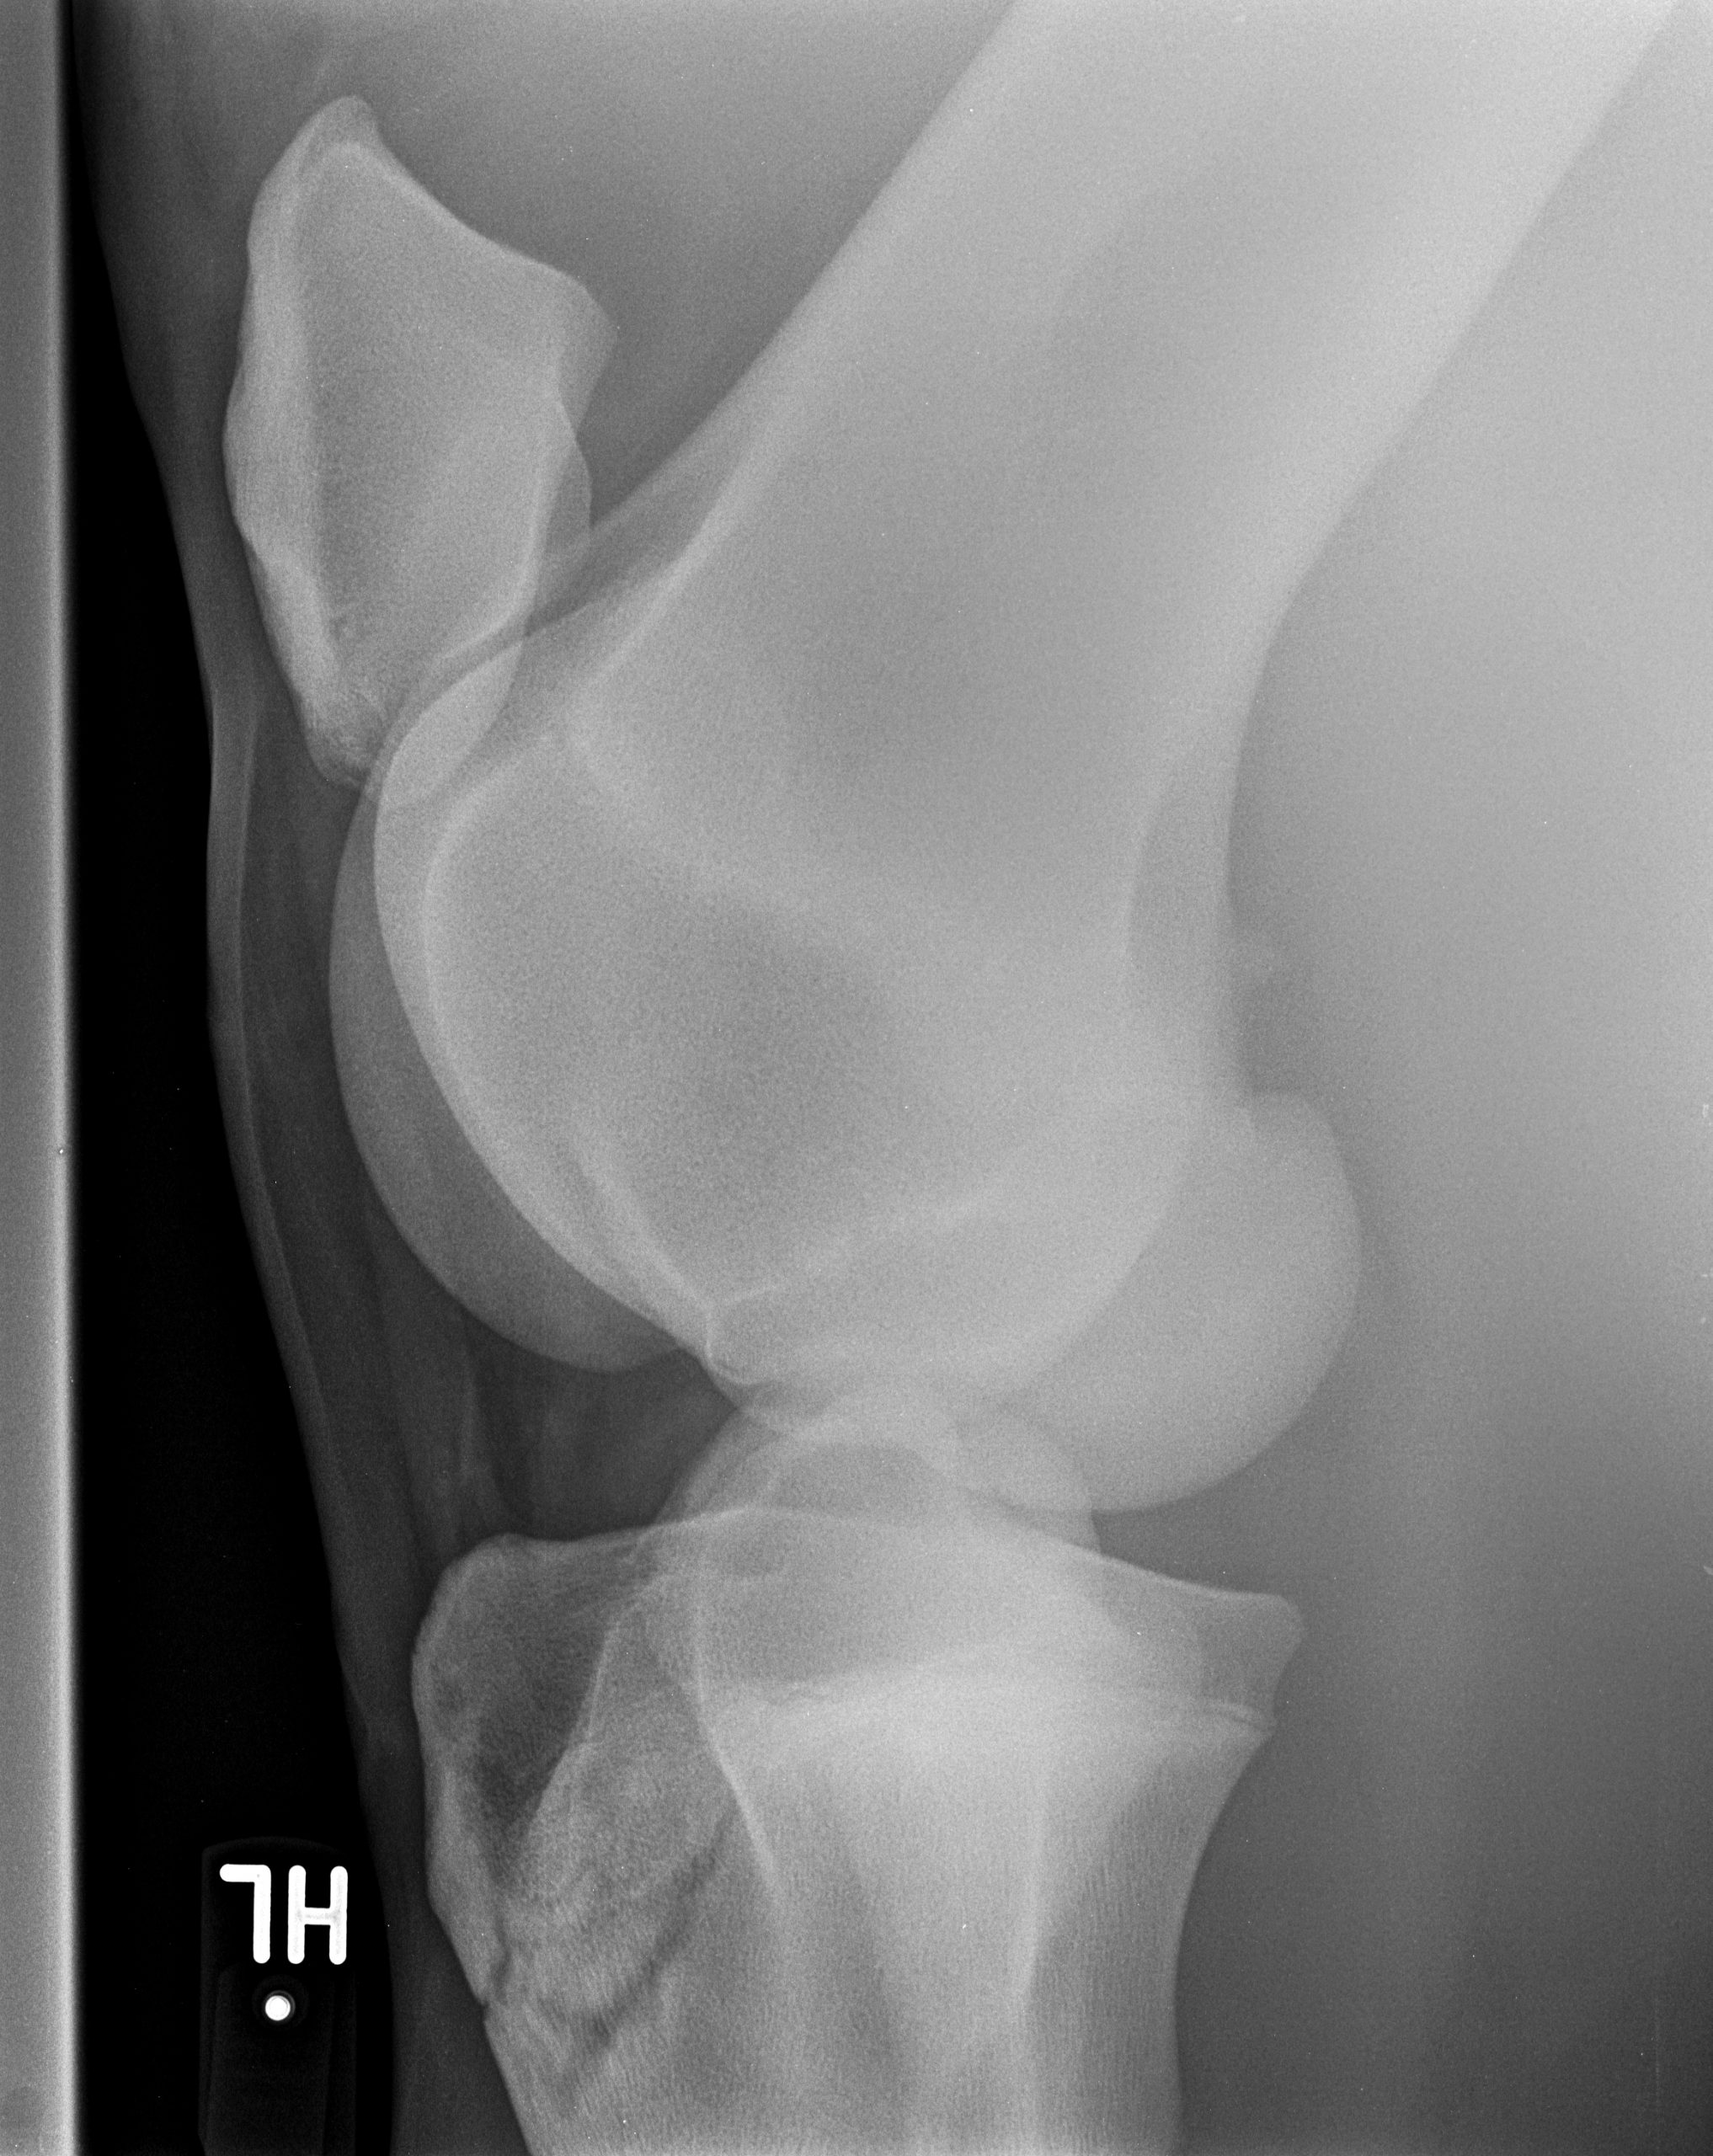

Röntgenbilder

Diese Sammlung zeigt verschiedene Röntgenaufnahmen, die eine Vielzahl von anatomischen Strukturen und potenziellen Gesundheitszuständen veranschaulichen. Jede Aufnahme bietet wertvolle Einblicke in die Gesundheit und das Wohlbefinden Ihrer Pferde.